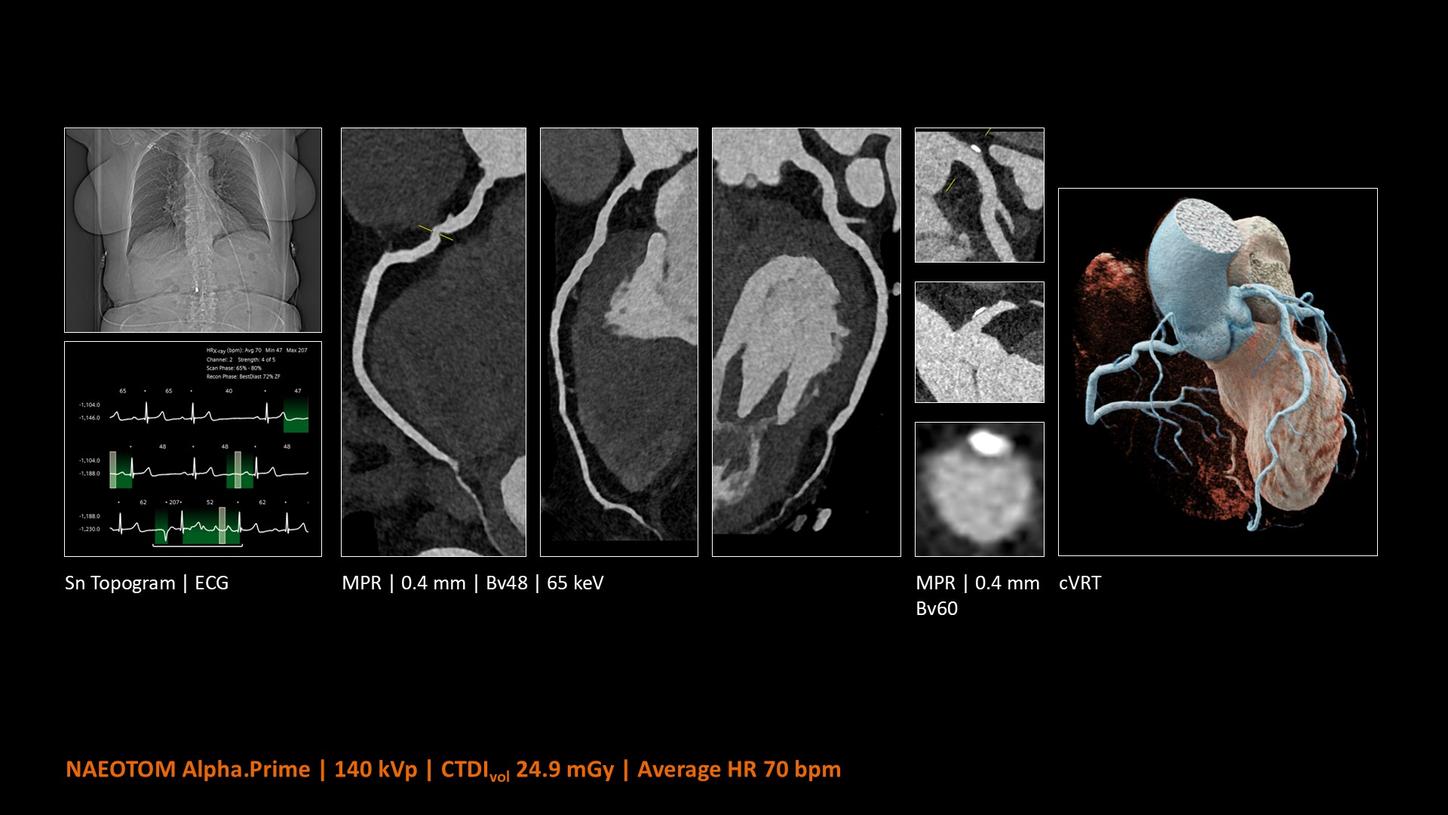

NAEOTOM Alpha® con Quantum Technology®, la nostra nuovissima Dual Source photon-counting CT, offre immagini Quantum HD Cardiac con uno spessore di slice di 0,2 mm. In questo modo è possibile visualizzare dettagli del cuore precedentemente non rilevabili senza incrementi di dose. Inoltre, le informazioni spettrali sono automaticamente disponibili in ogni scansione grazie a un processo di conversione diretta che trasforma i singoli fotoni dei raggi X in un segnale elettrico per creare l'immagine.

Quantum Technology consente una migliore valutazione diagnostica dei vasi coronarici nella TC. Secondo un recente studio, NAEOTOM Alpha e Quantum HD Cardiac potrebbero aver contribuito a ridurre la necessità di un'angiografia coronarica invasiva per il 54% dei pazienti nel rilevamento della malattia coronarica in una popolazione ad alto rischio.¹